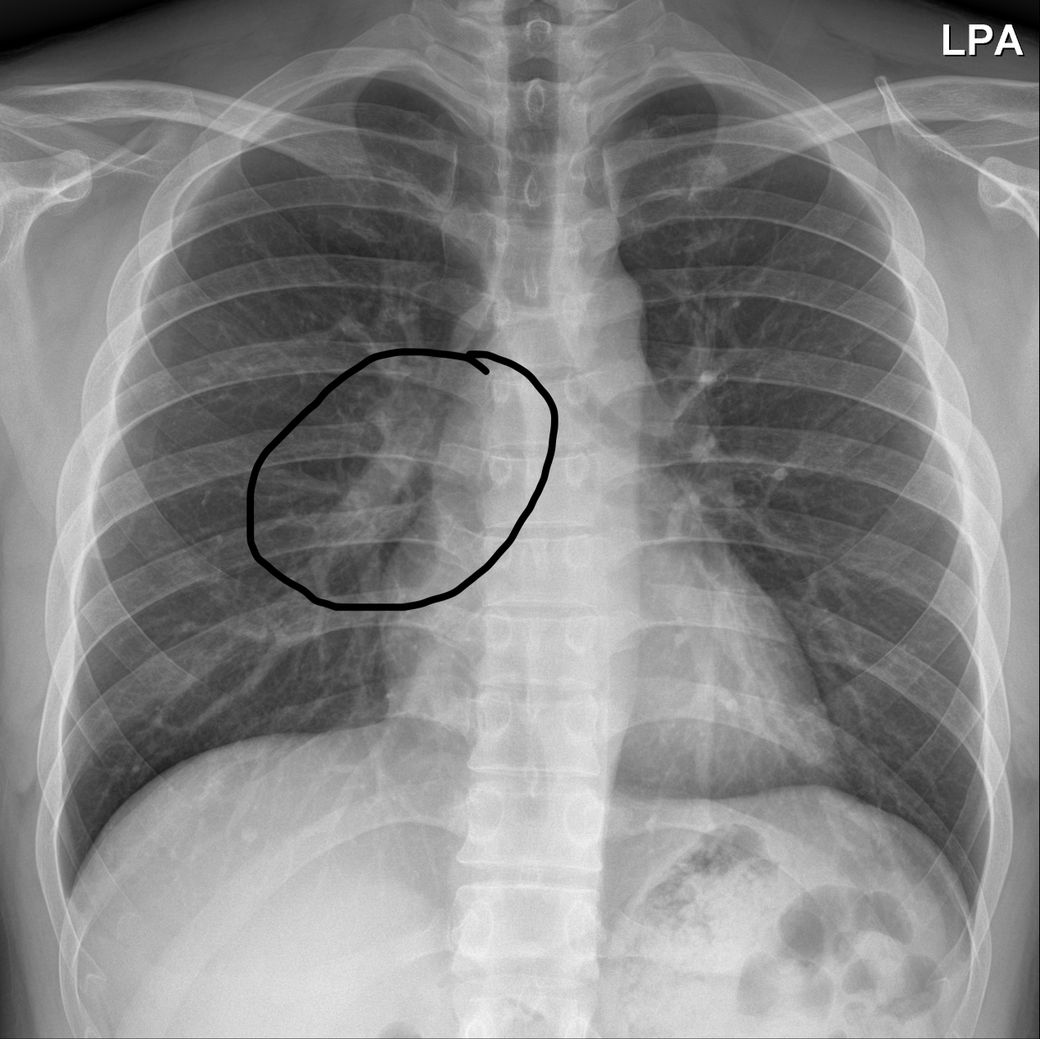

위 사진은 코로나가 없던 2018년의 엑스레이이고 아래는 2022년 코로나 감염 뒤 5개월 뒤 응급실에서 찍은 사진입니다.

엑스레이에서 특별한 이상은 보이지 않는다고 하셨는데, 우연히 2018년 찍은 사진과 비교해보니 동그라미 친 곳 안에 기관지로 보이는 하얀 관이 코로나 전에는 뚜렷하게 깨끗히 이어진 통로가 보이는 반면,

코로나 이후에는 마치 한지에 먹물 한 방울 떨어진 듯한 커다란 점 하나와 괴상하게 울긋불긋 머리털 솟은듯이 뻗어있거나 통로가 끊긴 것처럼 보이는데, 제가 전문가가 아니라서 조언을 구하고자 올립니다.

• 2번 째 사진

동그라미 친 부분은 폐혈관입니다.